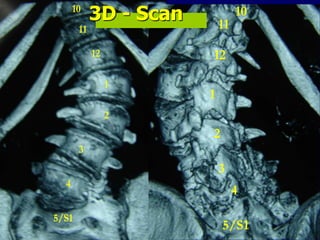

3 mts p.op. 12 11 1 2 3 4 5/S1 10 12 11 1 2 3 4 5/S1 103D

- Scan